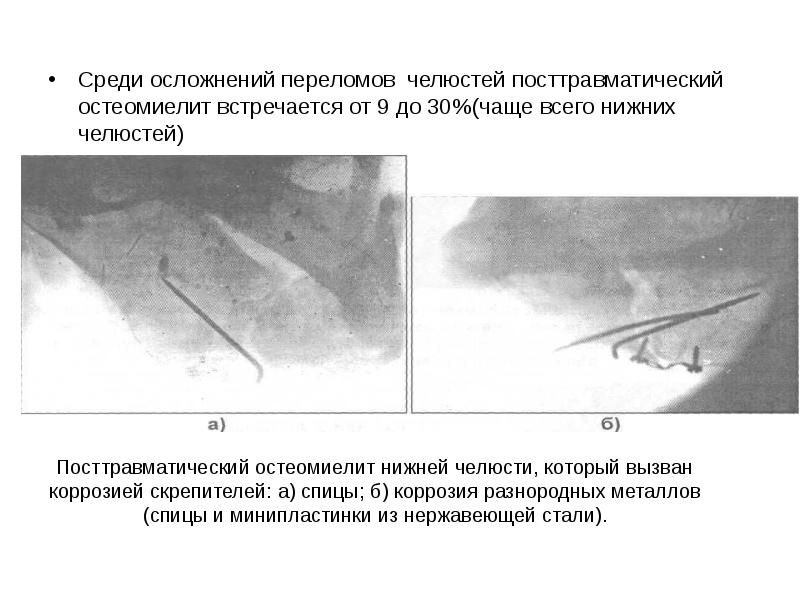

Рентгеновские снимки посттравматического остеомиелита челюсти: Медицинские случаи

Раздел: Образы вокруг